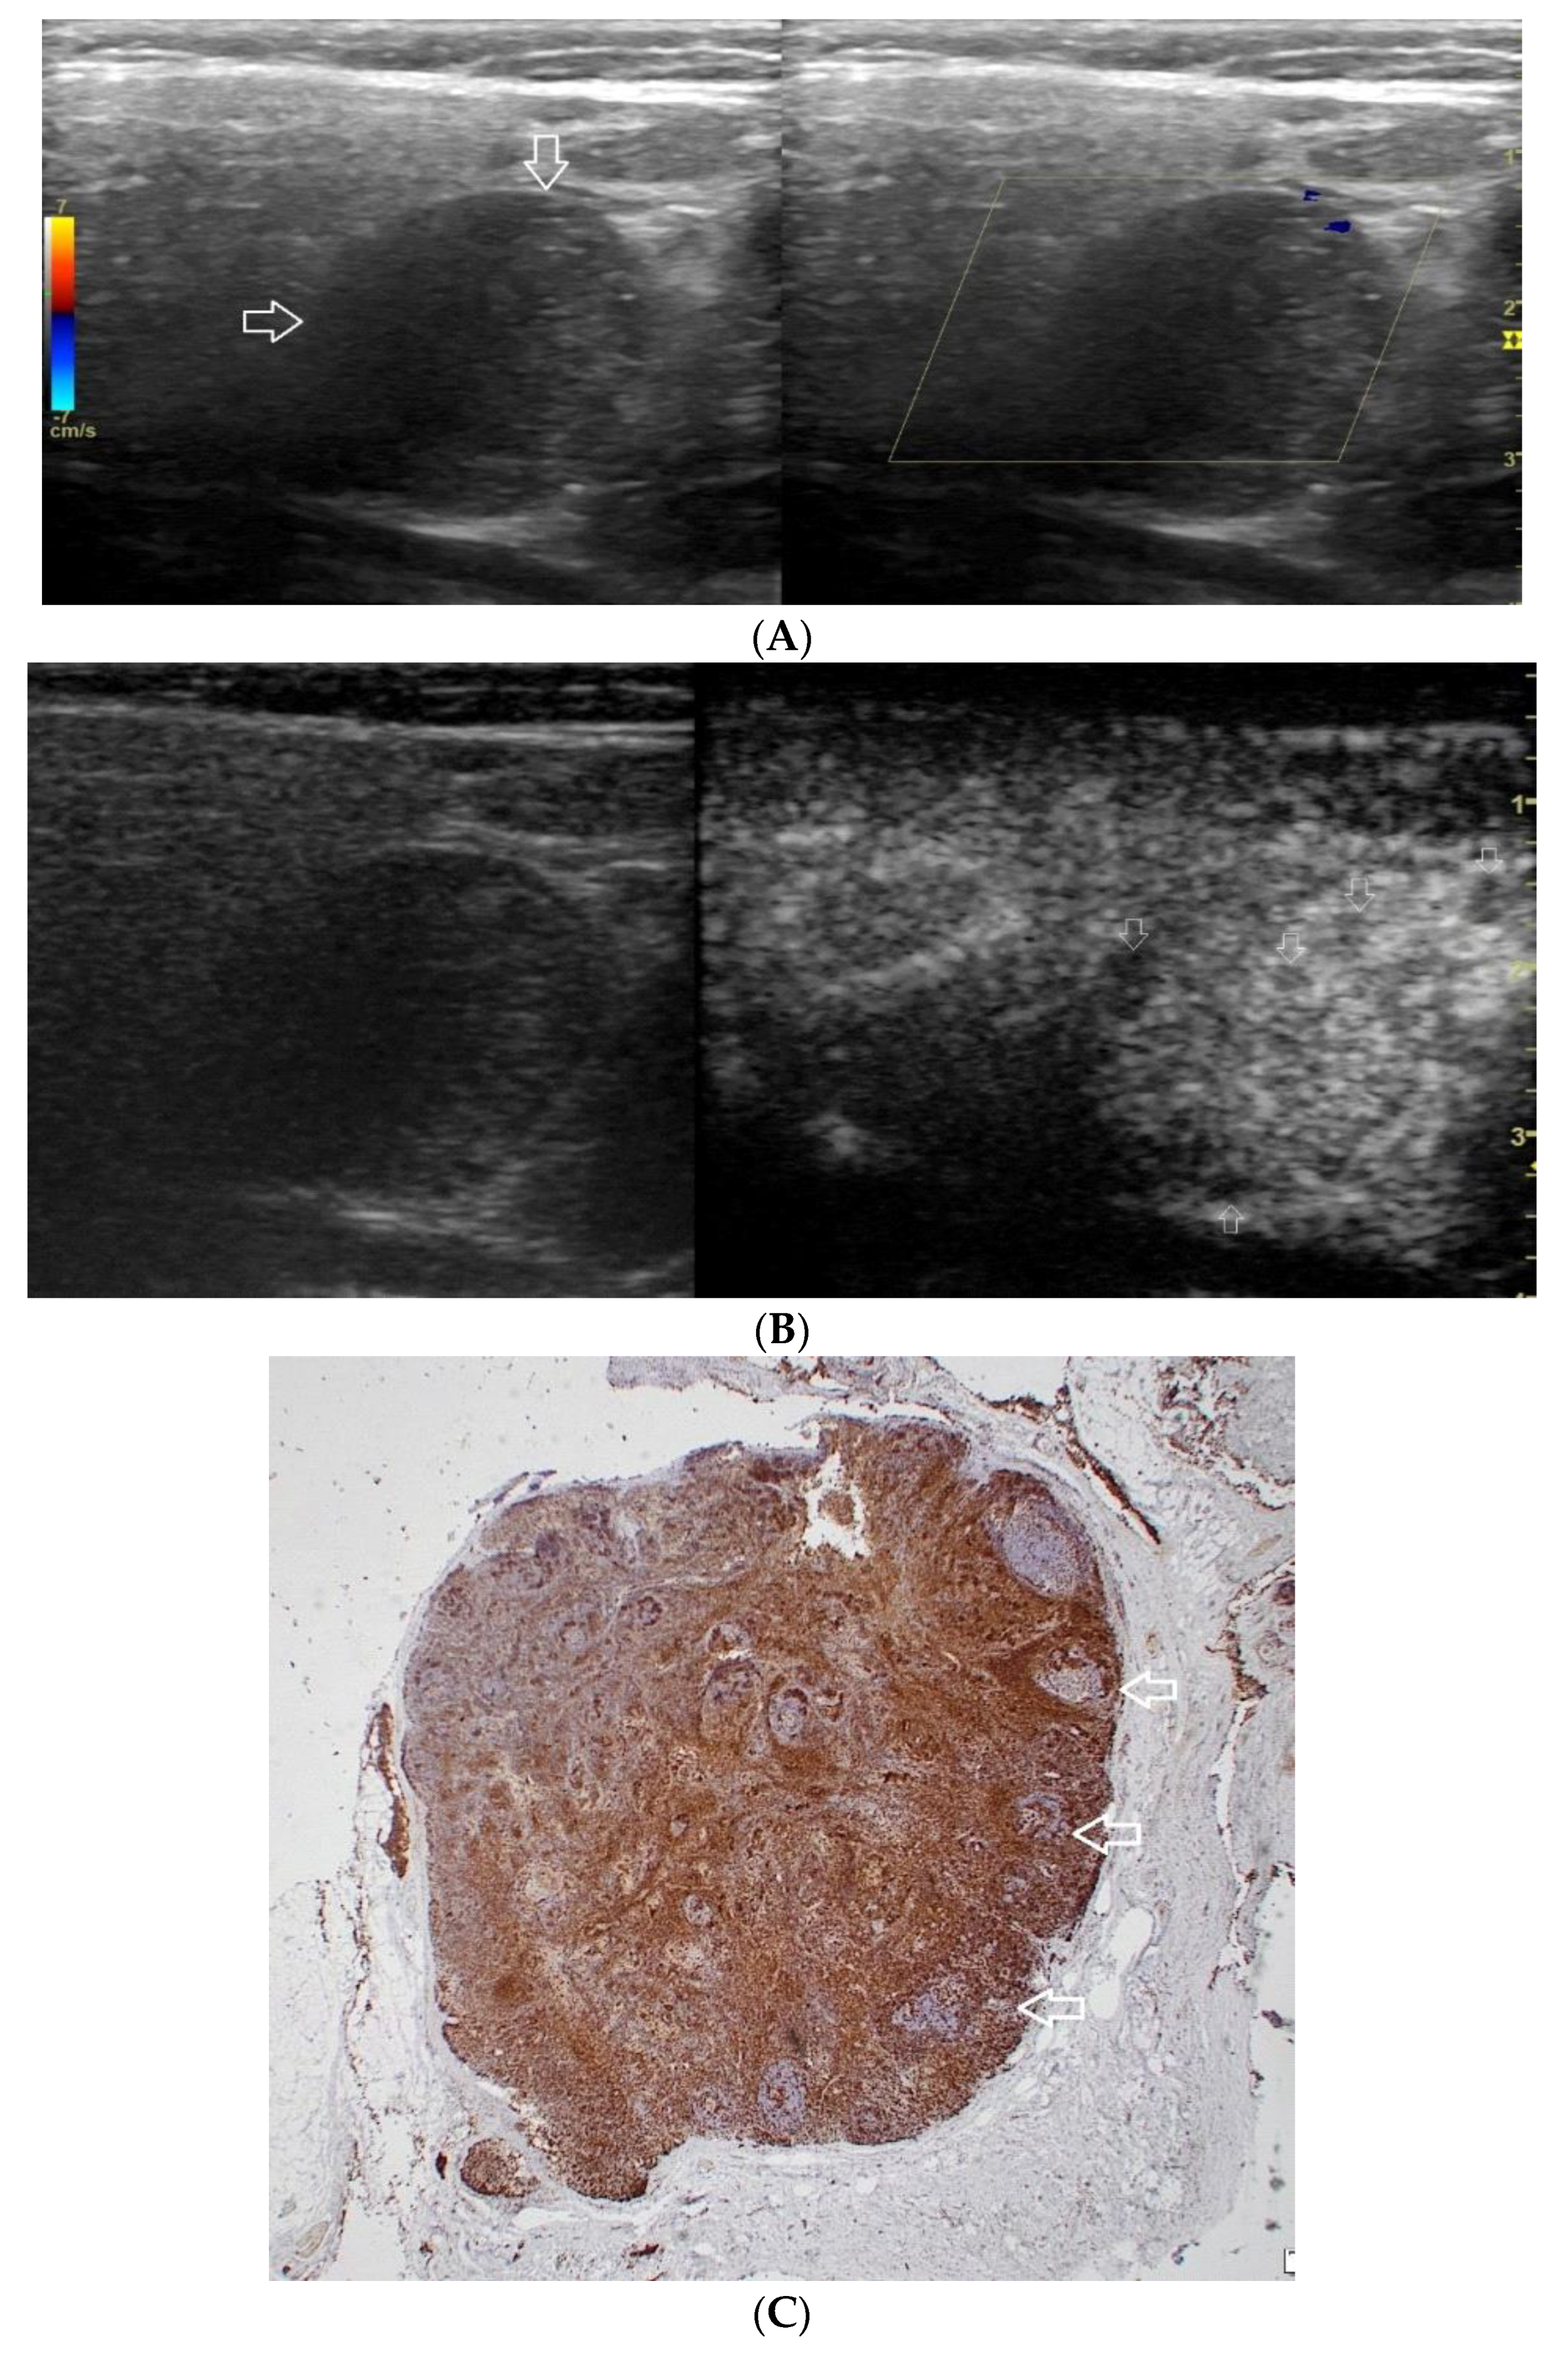

Figure 1.

(A−C) Lymphoepithelial carcinoma. (A) Routine ultrasonographic examination in B presentation and colour Doppler (CD): a hypoechogenic focal lesion of a heterogeneous echostructure (white arrows). On CD, low blood flow is observed. (B) Contrast-enhanced imaging in arterial phase: a strong heterogeneous enhancement of a lesion containing minor oval areas with no enhancement (white arrows). (C) Pathomorphological image, immunohistochemistry for CD3+. Aggregations of carcinomatous cells (white arrows) surrounded by scattered lymphoid tissue cells.